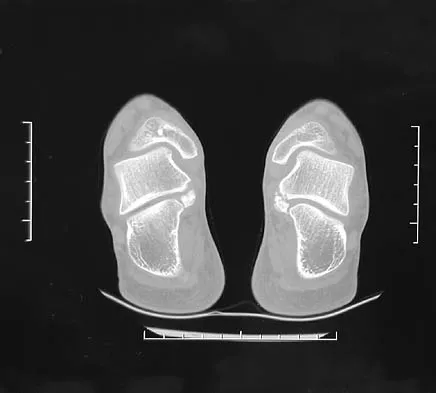

A 15-year-old boy has hindfoot pain and very limited subtalar motion. A CT scan reveals a talocalcaneal coalition involving 40% of the middle facet. He has no degeneration of the posterior subtalar facet. Following failure of nonsurgical management, treatment should consist of

Explanation